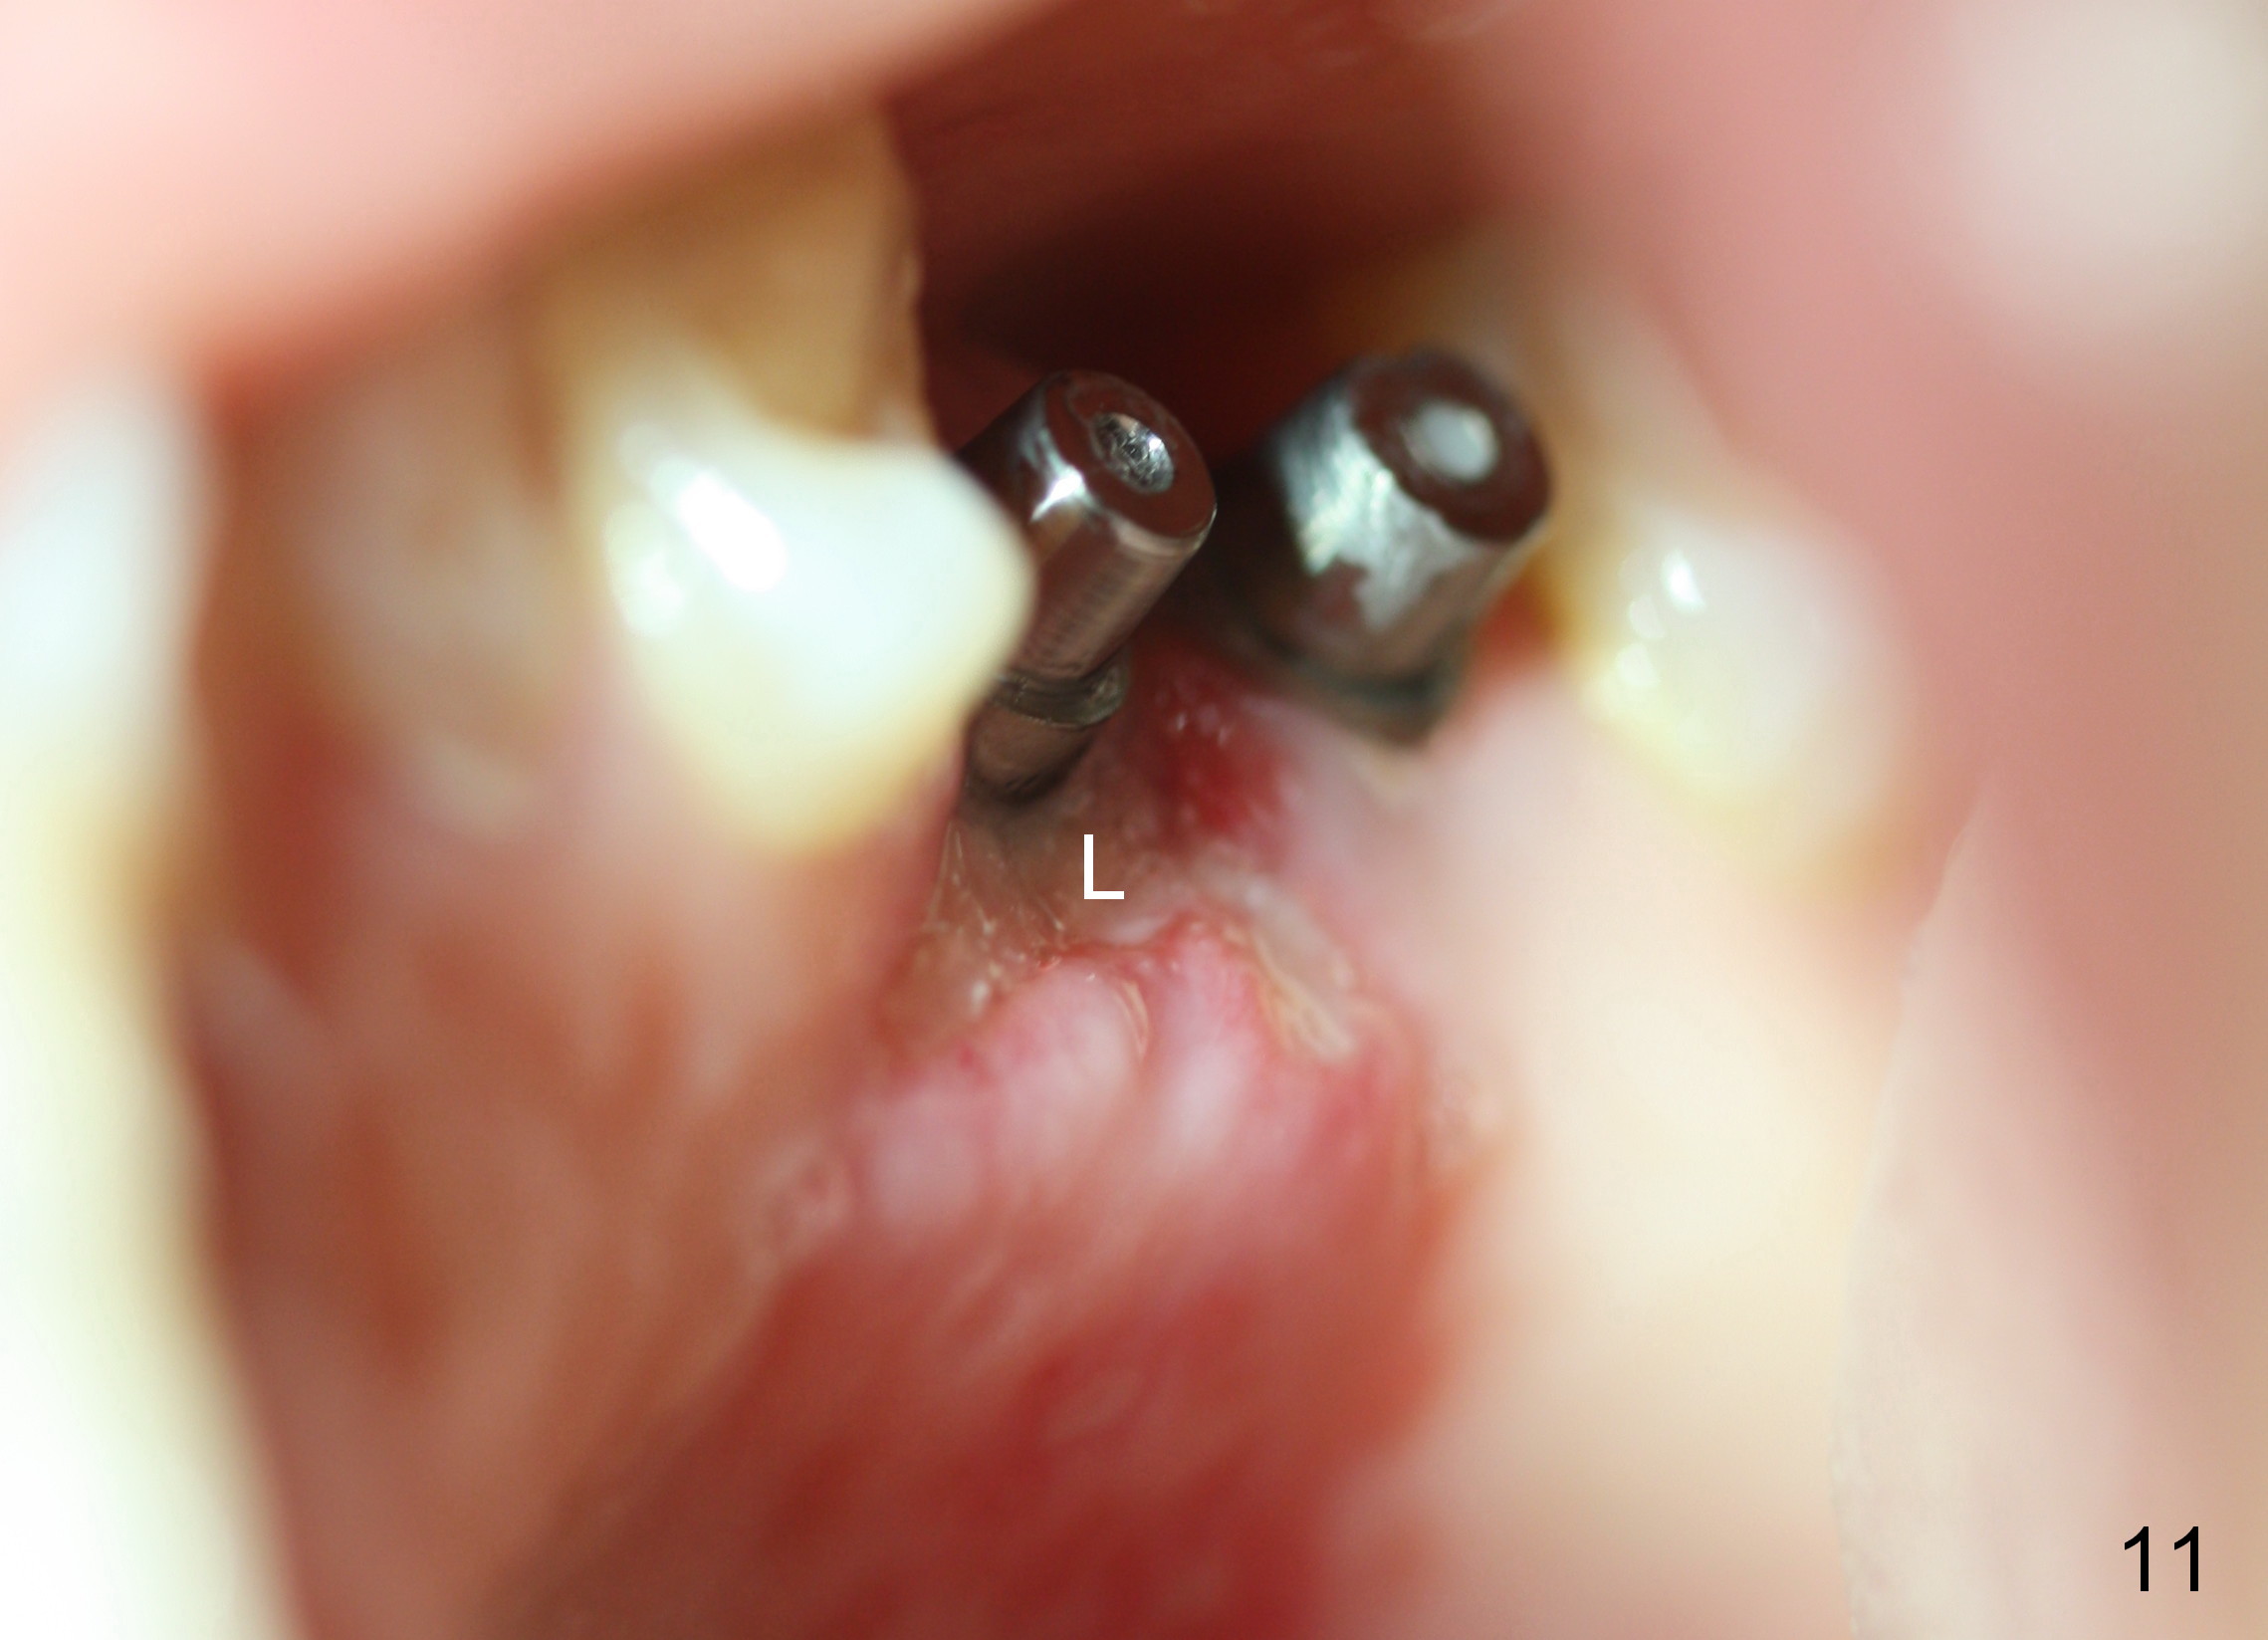

The patient returns for #13,14 implant placement. The ridge appears to be wide buccolingually (Fig.1 mirror view). A 4 mm tissue punch is used for access at the sites of #13 and 14. Osteotomy is initiated by using 3 mm trephine bur at the depth of 4 mm at both sites; 2 mm pilot drill is used to continue osteotomy at 8 mm deep at the site of #13. Sinus lift is accomplished by using tapered osteotomes 2,3 mm 6 mm deep, followed by 4.5x11 mm tap (Fig.2 T); 2 mm pilot drill (P) is reinserted into #13 osteotomy site with inadvertently penetrating the sinus floor. When the tap is removed from the site of #14, the sinus membrane is also found to be perforated. The sinus membrane at both sites is repaired by insertion of collagen dressing before bone graft. A 4x11 mm one-piece implant is placed at the site of #13 slowly hoping that it does not re-perforate the sinus membrane (Fig.3 O). Due to limited restorative height, the abutment portion of the one-piece is expected to be trimmed (Fig.4 O). In case of implant complication or failure, the implant may be difficult to be removed. Therefore the implant at the site of #14 is two piece one (Fig.4,5 I/A, 5x11 and 4x3 mm, respectively). The insertion torques for #13 and 14 are 35/40 and >60 Ncm. Immediate provisionals are canceled mainly because of patient's inability to open wide for long. Perio dressing is placed instead after adjustment of the height of the abutments. The patient experiences one episode of light nasal hemorrhage a few hours postop. Although the patient takes Amoxicillin for 1 week periop, the implant at the site of #13 dislodges 1 months postop (Fig.5). Immediate re-placement with a larger 2 piece one is canceled because of mild infection mesiobuccal to the implant at the site of #14 (Fig.6 >). Exploration around the latter implant reveals possible thread exposure in a small area. After copious irrigation with normal saline, Arestin is placed. Two months post exfoliation, the site is re-entered (Fig.7,8). There is a lingual defect. Osteotomy is initiated as buccal as possible. A 4.5x11 mm tapered tap penetrates the sinus floor without tearing the membrane (Fig.9). The same-sized implant is placed (25/30 Ncm) with sinus lift (Fig.10 *). The lingual defect is bone grafted. There is dehiscence lingually 7 days postop (Fig.11). Impression for final restoration is taken 1.5 months postop because of pending wedding. The crown has been in function for 2.5 months.